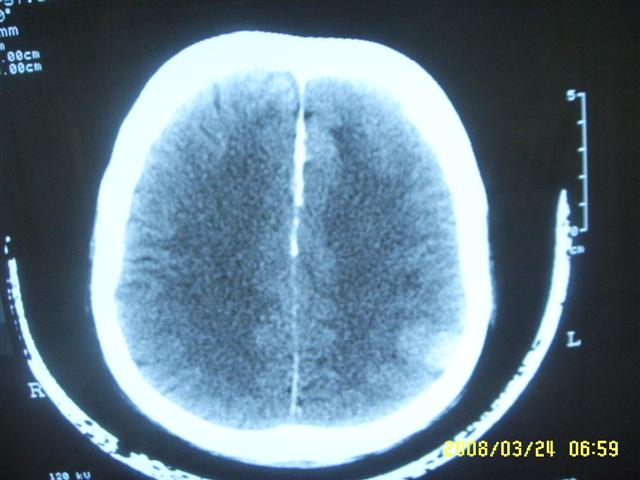

以下是引用dyqct在2008-4-2 20:09:00的发言:[br]考虑为:神经纤维瘤病(nf1型)。建议增强进一步检查。